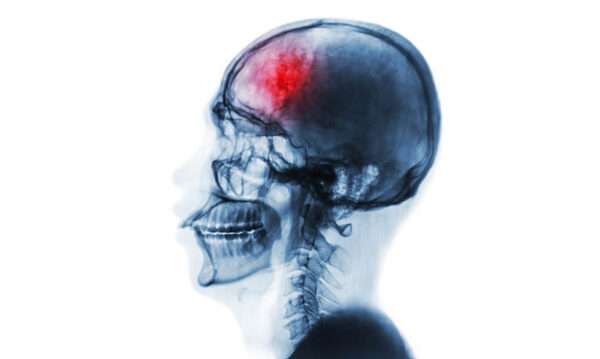

Las lesiones intracraneales, en su variedad de tipos, pueden ser una causa importante de cefalea debido a la alteración y desplazamiento de estructuras vasculares y otros tejidos sensibles al dolor dentro del cráneo. Este tipo de dolor de cabeza no es específico en cuanto a su localización, pero presenta patrones característicos que pueden ayudar en su identificación. En muchos casos, la cefalea asociada con una lesión intracraneal se agrava cuando la persona se recuesta, despertando al paciente durante la noche o alcanzando su intensidad máxima por la mañana, después de una posición recumbente prolongada durante la noche. Estos patrones son indicativos de la posible presencia de una masa intracraneal.

Además de estos síntomas sistémicos, los signos focales o difusos de disfunción cerebral, o los indicativos de un aumento de la presión intracraneal, como la presencia de papiledema (hinchazón del disco óptico debido a la presión intracraneal elevada), son indicadores cruciales que requieren investigación inmediata. El aumento de la presión dentro del cráneo es una situación grave que puede comprometer diversas funciones cerebrales y poner en riesgo la vida del paciente, lo que hace que la imagenología sea esencial para identificar la causa subyacente del dolor de cabeza y determinar el tratamiento adecuado.